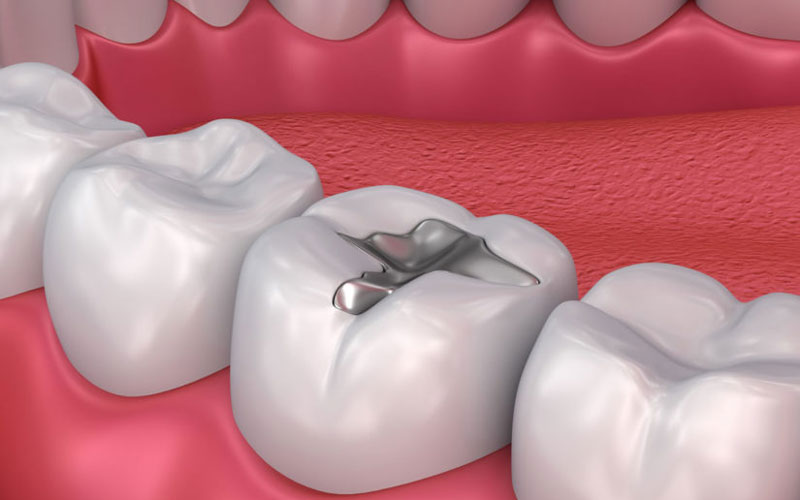

2.2 Trám hỗn hợp Bạc Amalgam

2.2.3 – Ưu điểm:

Giống với vàng, bạc cũng có đặc điểm kim loại nên có khả năng chịu lực nhai tốt, tuổi thọ của miếng trám cao, ít nhất từ 10-15 năm. Vật liệu hỗn hợp Bạc Amalgam có chi phí rẻ hơn nhựa Composite.

2.2.4 -Nhược điểm:

Tính thẩm mỹ hạn chế do hỗn hợp có sắc tố xám, không đều màu với màu răng tự nhiên. Có thể gây dị ứng do có lượng nhỏ thủy ngân trong hỗn hợp Amalgam. FDA công nhận sử dụng vật liệu Amalgam là an toàn cho người lớn và trẻ em từ 6 tuổi trở lên.